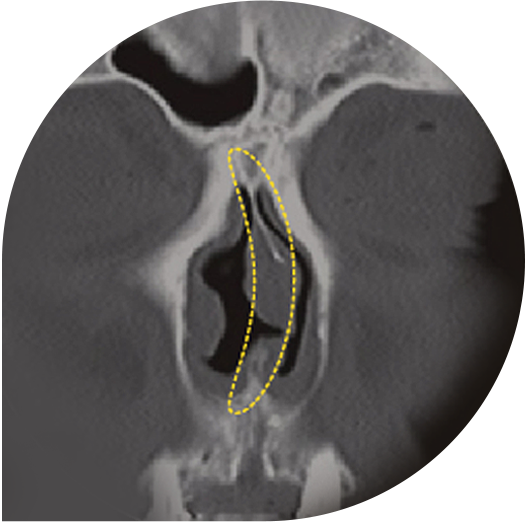

鼻弁狭窄症

鼻弁とは、鼻の中の空気が流れる鼻腔で最も狭い部位です。

正常な場合でも狭い部位であるため、この部位がさまざまな原因によって

さらに狭くなる状態を鼻弁狭窄症といいます。

鼻弁が狭くなると、

鼻づまりや睡眠障害を引き起こします。

鼻弁狭窄症の手術ノウハウ

狭くなった鼻弁を矯正するために、

鼻中隔とその側壁の間に軟骨を移植して鼻弁の幅を広げるくさび移植術を行います。

手術前 狭い鼻弁

鼻中隔軟骨と 鼻側壁の間に軟骨を移植

広がった鼻弁により 鼻弁狭窄症を矯正